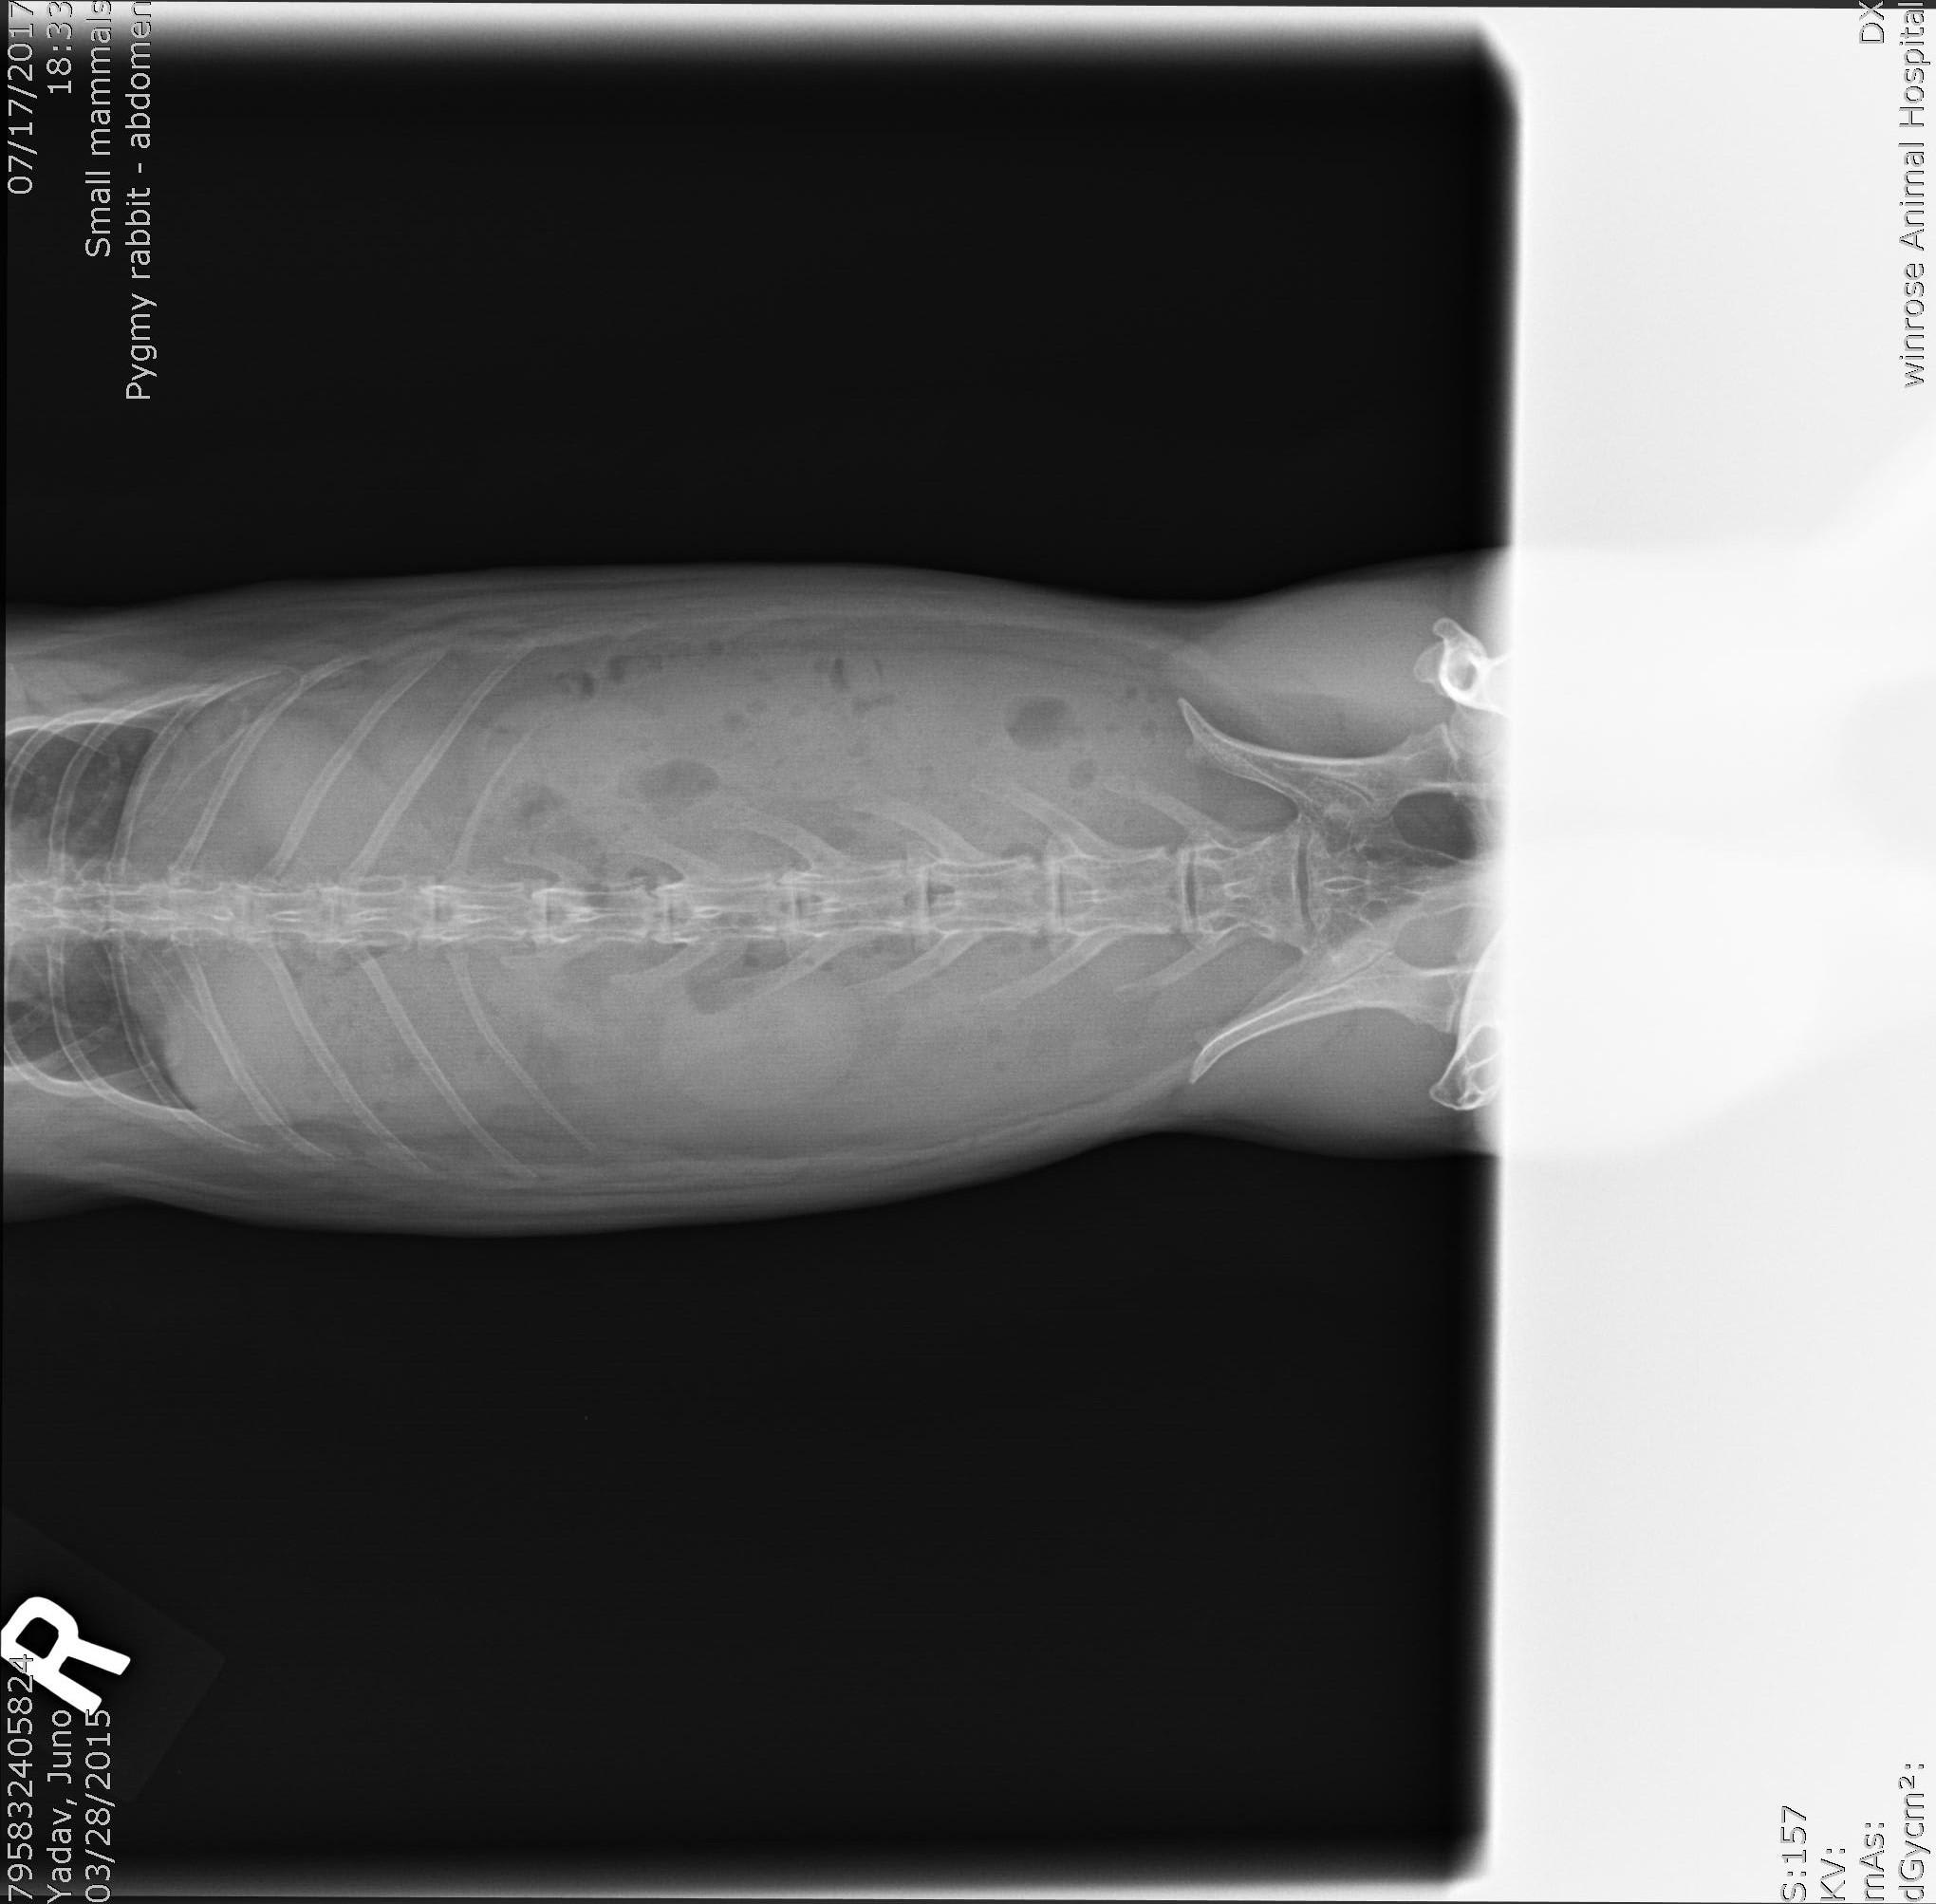

Hie there! I have a dutch dwarf bunny. Attached are his x-rays. Please can you take a look and advise me on pathological changes in them. History: Stopping pooping a week back, a vet noticed tenderness in his lower stomach area. He was put on Amoxicillin, cisapride and Eloxyn. After a week, pooping was still pretty small, weight loss of about 200 grams and food preference was only greens. I was feeding critical care but stopped because he was eating greens. This is the x-ray from day before.

There appears to be a lot of stool in the colon. I don't see any severe pathology though. I would recommend a few things: 1. STOP the Amoxcillin. I hate going against what another veterinarian has presbribed but Amoxicillin is not a good antibiotic for rabbits. It can be dangerous because of the likelihood of it negatively effect the GI Tract. I don't see any indication that an antibiotic is needed in your rabbit based on what you have stated in the history. 2. Continue the Cisapride and Eloxyn (if you still have some). The cisapride will help get the GI tract moving. He needs to stay on this drug until the motility of the GI tract is back to normal. 3. Keep feeding the Critical Care on top of the regular diet. Here is an article on GI stasis in rabbits that may help you. http://myhouserabbit.com/rabbit-health/gi-stasis-in-rabbits-a-deadly-condition/ They often take weeks to return to normal after being diagnosed with stasis. I hope this helps. Best wishes and I hope Juno gets back to normal soon!